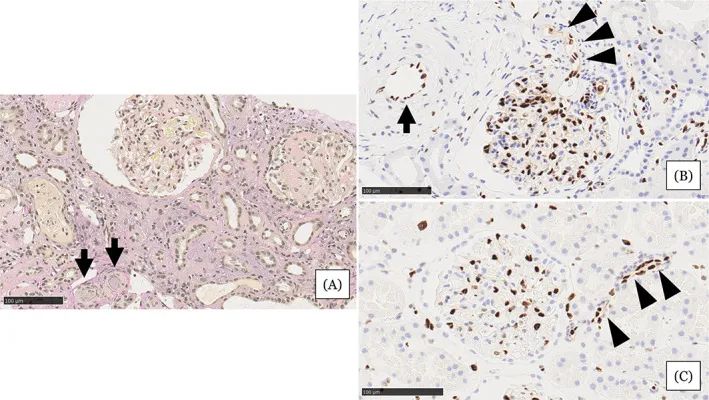

在住院第31天進(jìn)行的腎活檢結果

圖注:在住院第31天進(jìn)行的腎活檢結果。A,顯示小動(dòng)脈被粘液性?xún)饶ぴ龊瘢^)堵塞,腎小球萎縮,毛細血管壁起皺,嚴重的間質(zhì)單核細胞浸潤伴腎小管損傷。B,EC細胞核的缺乏在小動(dòng)脈(箭頭)中很突出。在相鄰的小動(dòng)脈(箭頭)中注意到不同大小的不規則細胞核。C,EC的等距核在血壓正常的腎臟供體的腎臟小動(dòng)脈中形成有序的線(xiàn)。比例尺 =100μm